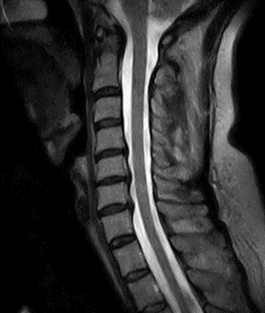

様々な部位や疾患の検査において幅広い診断情報を得るために、当院では整形外科の検査に特化した最新のオープン型MRIを導入しております。

X線一般撮影では判別しづらい骨折や骨のダメージ、靭帯など軟部組織の精査が可能です。

背骨や関節の検査に特化したMRIです。独自開発された患部ごとに対応した高感度専用コイル(体内からの信号を受信するアンテナ)と最新の画像技術により、超電導型にせまる高画質を実現しています。